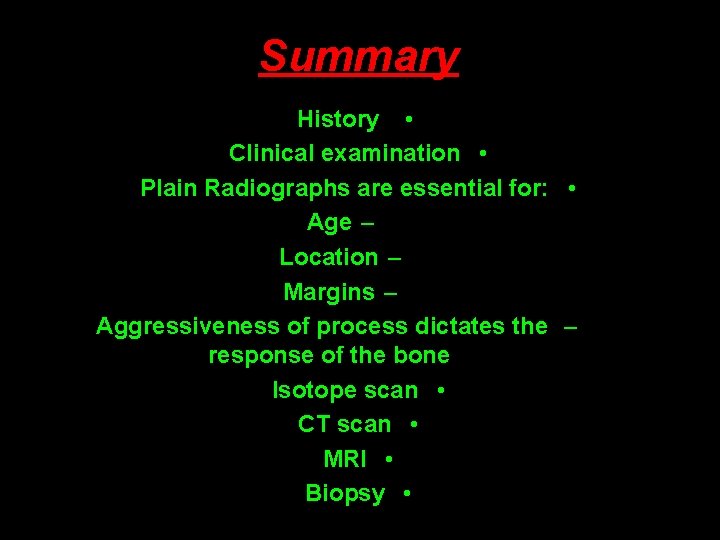

Summary History • Clinical examination • Plain Radiographs are essential for: • Age – Location – Margins – Aggressiveness of process dictates the – response of the bone Isotope scan • CT scan • MRI • Biopsy •